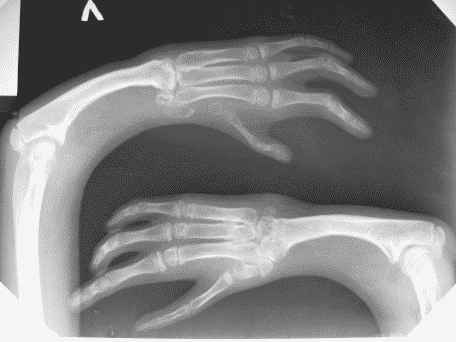

Мальчику 12 лет, страдает аномалией развития верхних конечностей.

Ребенок был оперирован несколько раз в другом городе. На сегодняшний день у пациента выражена деформация левого предплечья и оба предплечья короткие. У пациента и родителей есть желание удлинить предплечья.

Функция кистей нарушена, сгибание в локтевых суставах в полном объеме.

Движение в локтевых суставах в полном объеме (сгибание- разгибание)В лучезапястных суставах движения минимальны в диапазоне 5/0/5градусов.